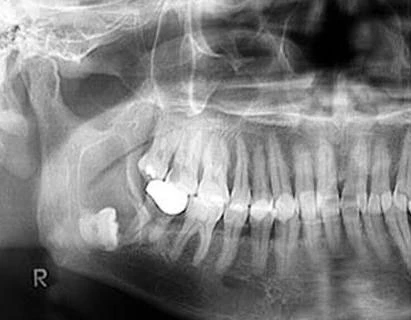

X-quang không cho hình ảnh đặc hiệu, thường là hình đa nang cho phép ta nghĩ tới u men:

+ Có nhiều đám tròn hay Oval, kích thước không bằng nhau, đồng dạng, ít cản quang, bờ mảnh và đều, tựa vào nhau và chồng lên nhau cho ta hình ảnh “bong bóng xà phòng”. Vỏ xương hàm bị mỏng dần, có chỗ bị u đẩy phồng lên.

+ Nhưng hay gặp là hình thấu quang rộng, giới hạn bằng nhiều đường viền ở xung quanh, có các vách xương mảnh ngăn cách ở giữa tạo thành nhiều xoang.

+ Ở giai đoạn muộn, u men cho hình ảnh một buồng thấu quang lớn, bờ nham nhở, u làm vỏ xương mỏng đi dần và phồng lên. Ở hàm dưới nó có thể đẩy phồng hõm Sigma nhưng lồi cầu vẫn giữ được hình dạng.

+ Kiểm tra kỹ trên X-quang có thể thấy:

* U không xâm lấn vào phần mềm.

* Thường gặp hình ảnh tiêu chân răng do u phát triển chậm.

* ống răng dưới có thể bị đẩy về một phía.

* Có thể phát hiện thấy các ổ tổn thương nhỏ khác ở cách xung quanh ổ tổn thương chính, điều này quan trọng trong việc đưa ra phương hướng điều trị.